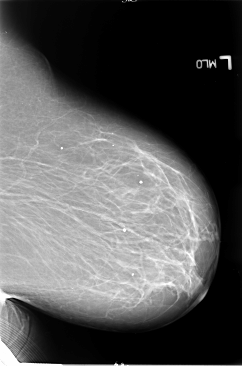

B_3065_1.LEFT_MLO

LEFT_MLO LINES 5856 PIXELS_PER_LINE 3864 BITS_PER_PIXEL 12 RESOLUTION 50 NON_OVERLAY